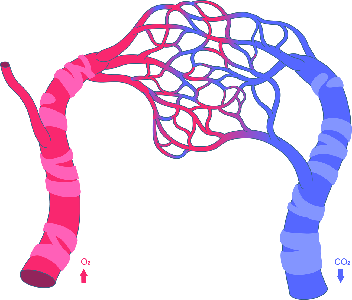

Detailreiche Fotografien aus der medizinischen Praxis ergänzen die Texte; moderne, genaue,

wissenschaftliche Zeichnungen geben Einblick in die Anatomie und die Funktion der Lunge und

anderer Organe.